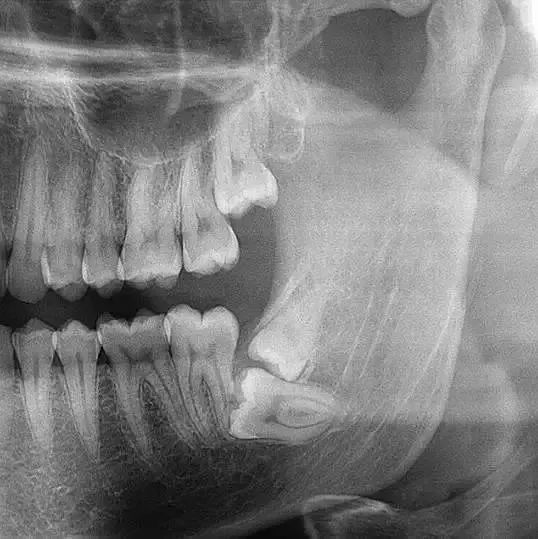

複雜阻生牙

人地常講嘅壓力大

後牙痛,好多時候都係因為呢個

▲德國聖路易斯全景影像

係可以幫醫生檢查治療牙齒嘅

提供好重要嘅參考啊